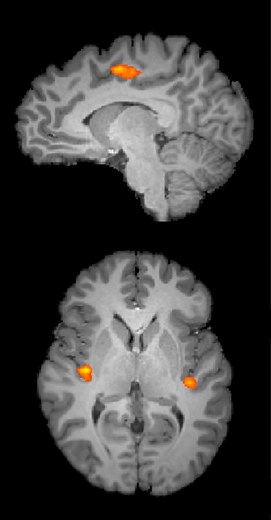

When people worry about math, the brain feels the pain

2012年10月31日

uchicago.edu